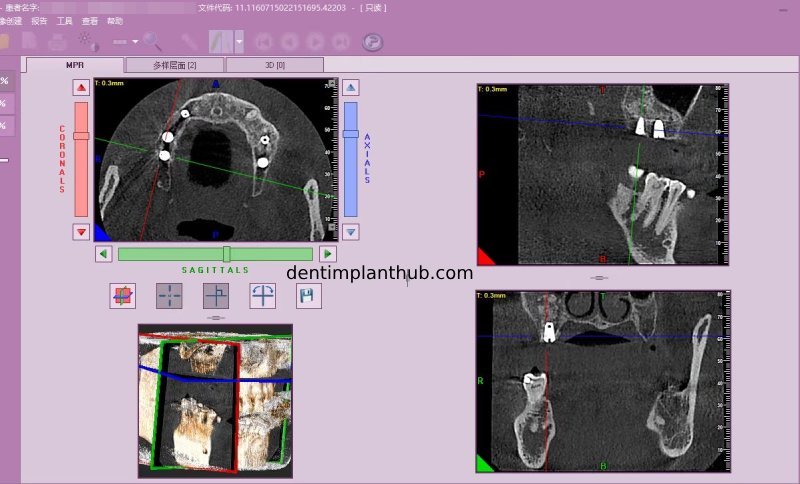

Screenshot of repeat CT on 7/1/25